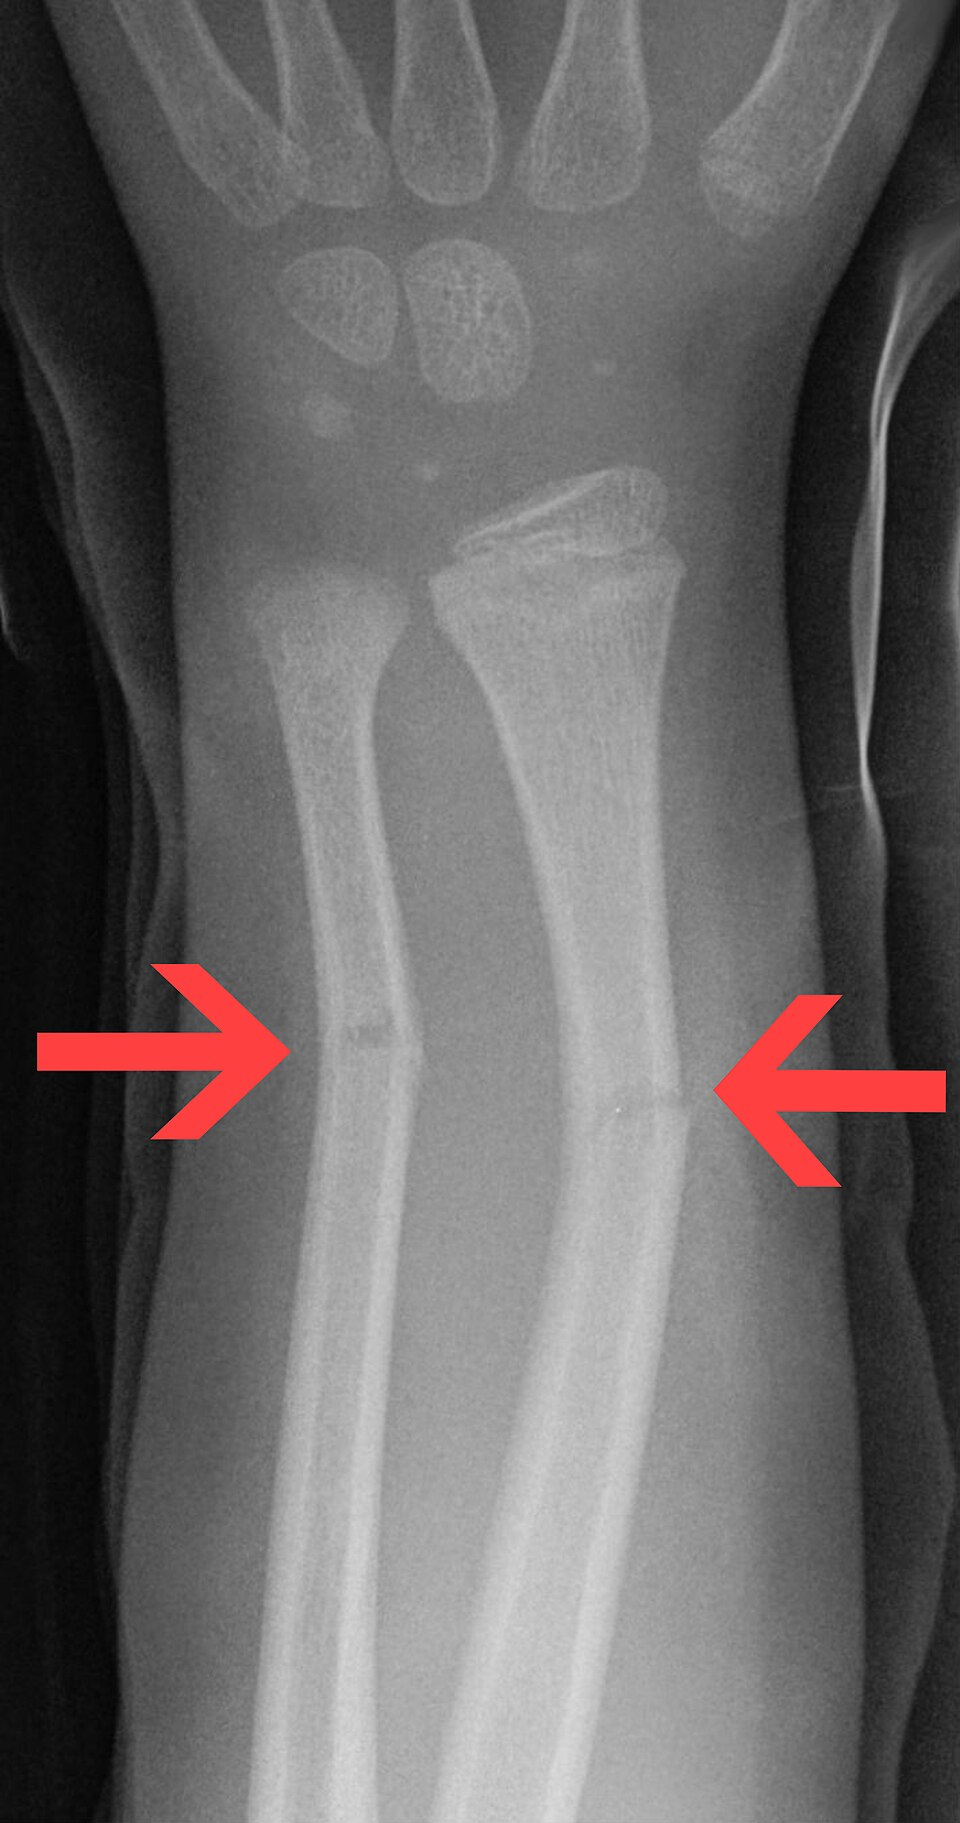

• 융기 골절 (Torus Fx.): 뼈의 한쪽 피질(cortex)만 압축되어 볼록하게 튀어나오는(buckling) 골절

• 생목 골절 (Greenstick Fx.): 뼈의 한쪽 피질은 부러지고(tension side failure) 반대쪽 피질은 휘어지는(bending/compression side intact) 골절